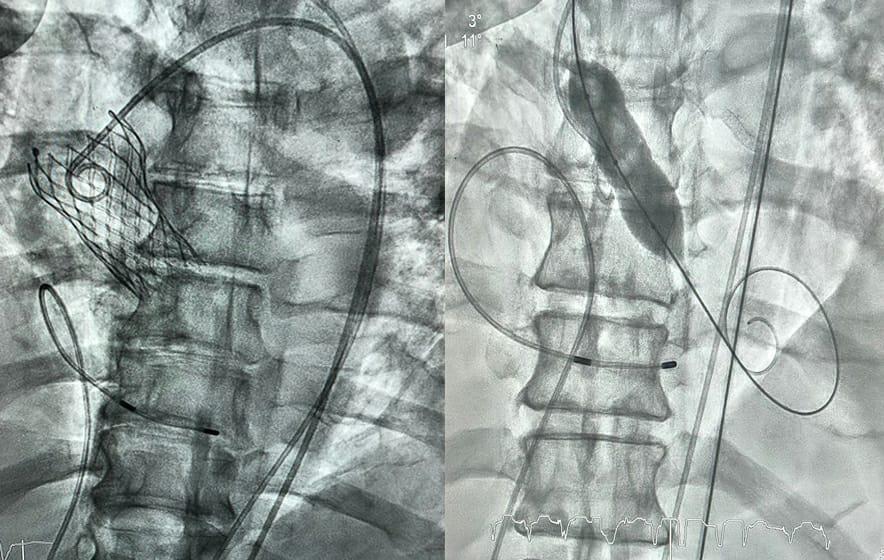

وأجريت عملية التغيير تحت التخدير الموضعي دون الحاجة للتخدير الكامل حيث قام الفريق الطبي بتجاوز الصمام المتضيق وزراعة صمام جديد عن طريق القسطرة القلبية عبر فتحة صغيرة في الفخذ الأيمن، وبعد زراعة الصمام زادت مساحة الفتحة الخارجية له الى “٢.٤” سم مربع، وانخفض ضغط الدم إلى المعدل الطبيعي، وكذلك تحسنت وظائف القلب وضغط التجويف الداخلي، وهو ما أدى بفضل الله إلى استقرار حالة المريض، ومغادرته للمستشفى بعد “24” ساعة.